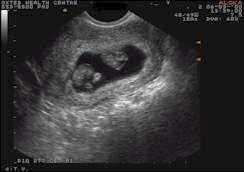

Your first pregnancy scan, often the "dating scan," is usually around 11-14 weeks to confirm pregnancy, determine your due date, check development, and screen for conditions like Down's syndrome.

Early scans (6-9 weeks) may be offered for reassurance or medical reasons, checking viability, heartbeat, and number of babies, using ultrasound to measure growth and assess the uterus.

Preparation often involves a full bladder for clearer images, and these scans are vital for confirming the pregnancy is progressing normally.